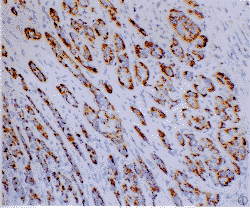

2.2 不同类型热休克蛋白表达的定位及阳性率 食管组织经免疫染色后,阳性颗粒呈浅棕色到深褐色。HSP25和HSP60阳性表达产物位于细胞浆,分别呈弥漫细颗粒和弥漫粗颗粒状;HSP70阳性部位位于细胞核,呈灶性或弥漫性阳性(图1,2)。癌旁增生的食管粘膜阳性部位HSP25、HSP60和HSP70分别位于食管粘膜上皮的不全角化层、全层细胞和棘细胞层内,阳性率分别为50.0%、92.3%和61.5%;切缘食管粘膜3种HSPs仅极少数细胞呈低水平表达。不同类型HSPs在51例食管癌的表达及阳性程度详见表1。

图1 食管鳞状细胞癌,癌细胞浆HSP-60蛋白阳性.SABC法,苏木素复染×100

图2 食管鳞状细胞癌,癌细胞浆HSP-70蛋白阳性.SABC法,苏木素复染×200